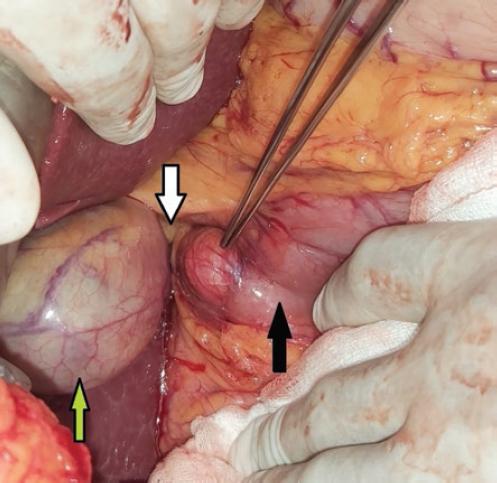

Se programa de manera electiva para colecistectomía y exploración de la vía biliar, la cual se realiza sin complicaciones, con los siguientes hallazgos: divertículo en la segunda porción del colédoco de 5 × 5 cm, vesícula biliar de 15 × 5 × 2 cm y colédoco de 3 cm de diámetro con múltiples litos (seis en total), el de mayor tamaño de 3 × 3 × 2 cm. Se realiza dilatación del ámpula de Vater. El tiempo quirúrgico fue de 150 minutos y el sangrado fue de 100 ml (Fig. 5).

Figura 5 Divertículo duodenal señalado con la pinza de disección, colédoco (flecha blanca), duodeno (flecha negra) y vesícula biliar (flecha verde).